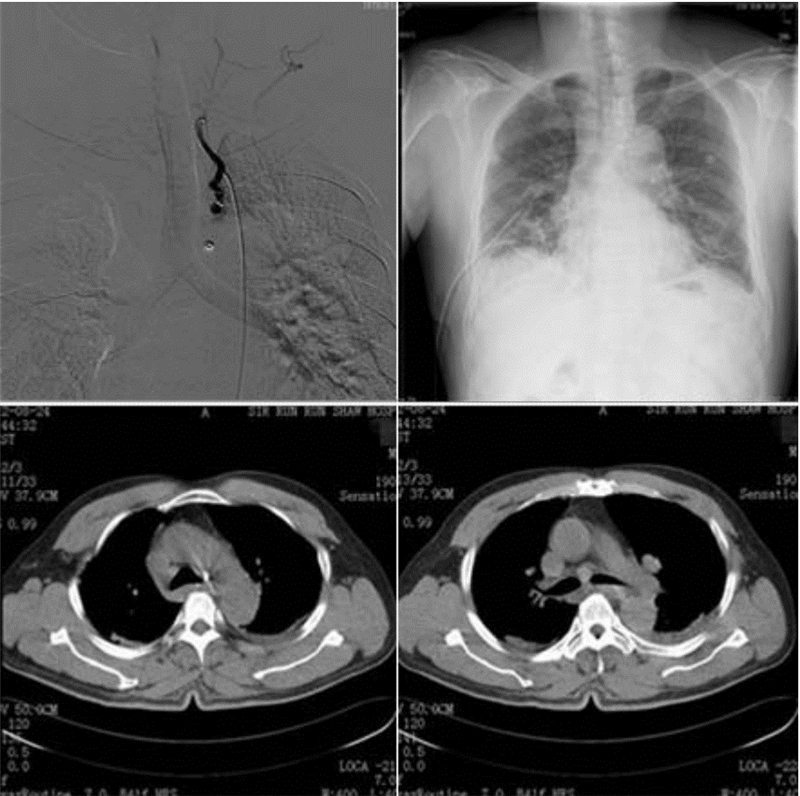

1 资料与方法患者,男性,52岁。因“突发右侧胸痛伴头痛1 d”急诊入院。查体:体温37.2 ℃,心率106次/min,呼吸20次/min,血压147/92 mmHg(1 mmHg=0.133 kPa)。神清,精神软,聋哑,双侧瞳孔等大等圆,光反应灵敏,颈静脉不充盈,气管居中,左肺及右上肺呼吸音清,右中下肺呼吸音消失,叩诊呈浊音,未闻及干湿啰音。心律齐,无杂音,腹平软,无压痛,双下肢无水肿。否认高血压、糖尿病、冠心病史;否认肺结核、支气管扩张征病史;否认药物食物过敏史;否认外伤手术史。血常规:白细胞计数10.4×109 L-1,血红蛋白13.5 g/dL,血小板计数173×109 L-1,中性粒百分数86.5% ;生化提示:电解质、肝肾功能及心肌酶谱正常;凝血功能提示正常。增强CT提示:(1)右肺广泛渗出改变,右下肺部分实变;左肺舌段少许炎症灶;(2)右侧胸腔积液。(3)气管隆突下结节状强化明显,旁边小血管影;后纵隔软组织肿块片,考虑血肿破入右侧胸腔可能(图 1)。立即急诊行主动脉造影+异位支气管动脉(假性动脉瘤)栓塞术,术中见主动脉造影见左侧锁骨下动脉发出异位支气管动脉,异位支气管动脉增粗,于隆突水平呈囊袋样扩张,给予栓塞治疗。术中用5F Cobra导管及微导管超选至异位支气管动脉内,先注入明胶海绵约一片,造影示异位支气管动脉末梢分支消失,但假性动脉瘤仍可显示,然后经微导管释放宝塔型弹簧钢圈2 mm~6 cm×1个,4 mm~8 cm×1个,术后造影示异位支气管动脉闭塞,假性动脉瘤未见显影。介入栓塞后再行右侧胸腔闭式引流治疗。术后恢复良好,第9天出院。术后22 d复查胸部增强CT,异位支气管动脉栓塞术后改变,血栓形成,未见强化影(图 2)。

![]() |

| 图 2 术后造影,术后胸片和术后胸部CT结果 |